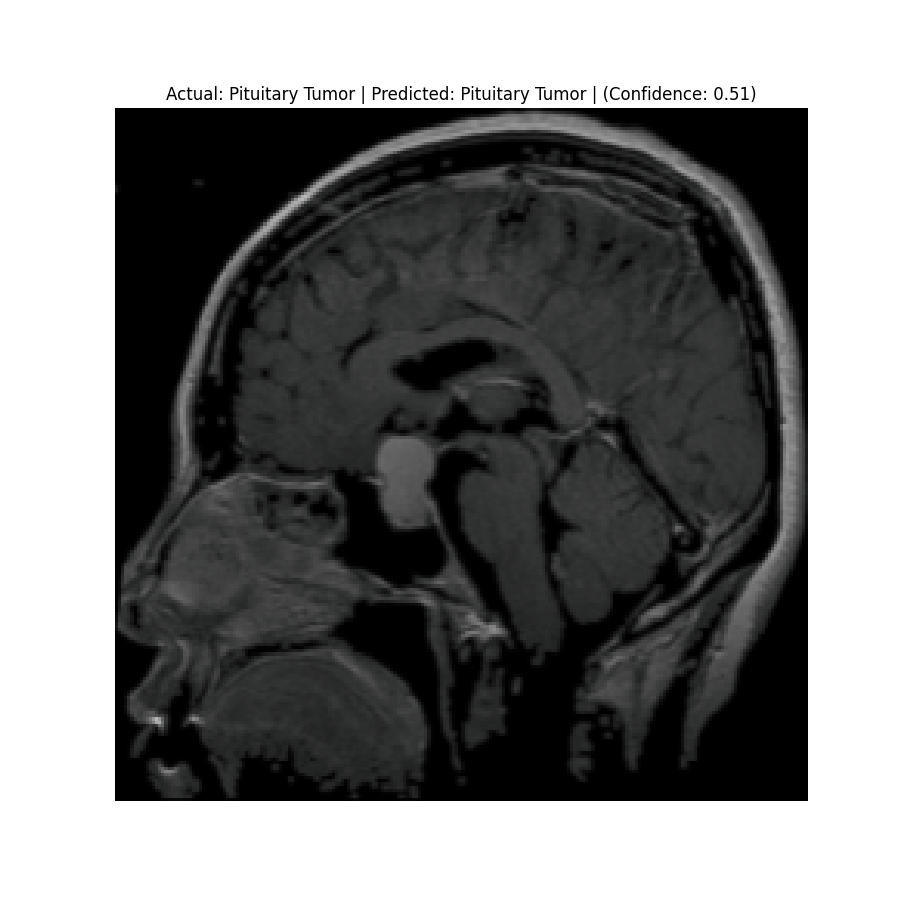

Check the predictions in the predictions folder. Below are some sample results:

![]() Actual: Pituitary Tumor Predicted: Pituitary Tumor (Confidence: 0.51) | ![]() Actual: Pituitary Tumor Predicted: Meningioma Tumor (Confidence: 0.43) |